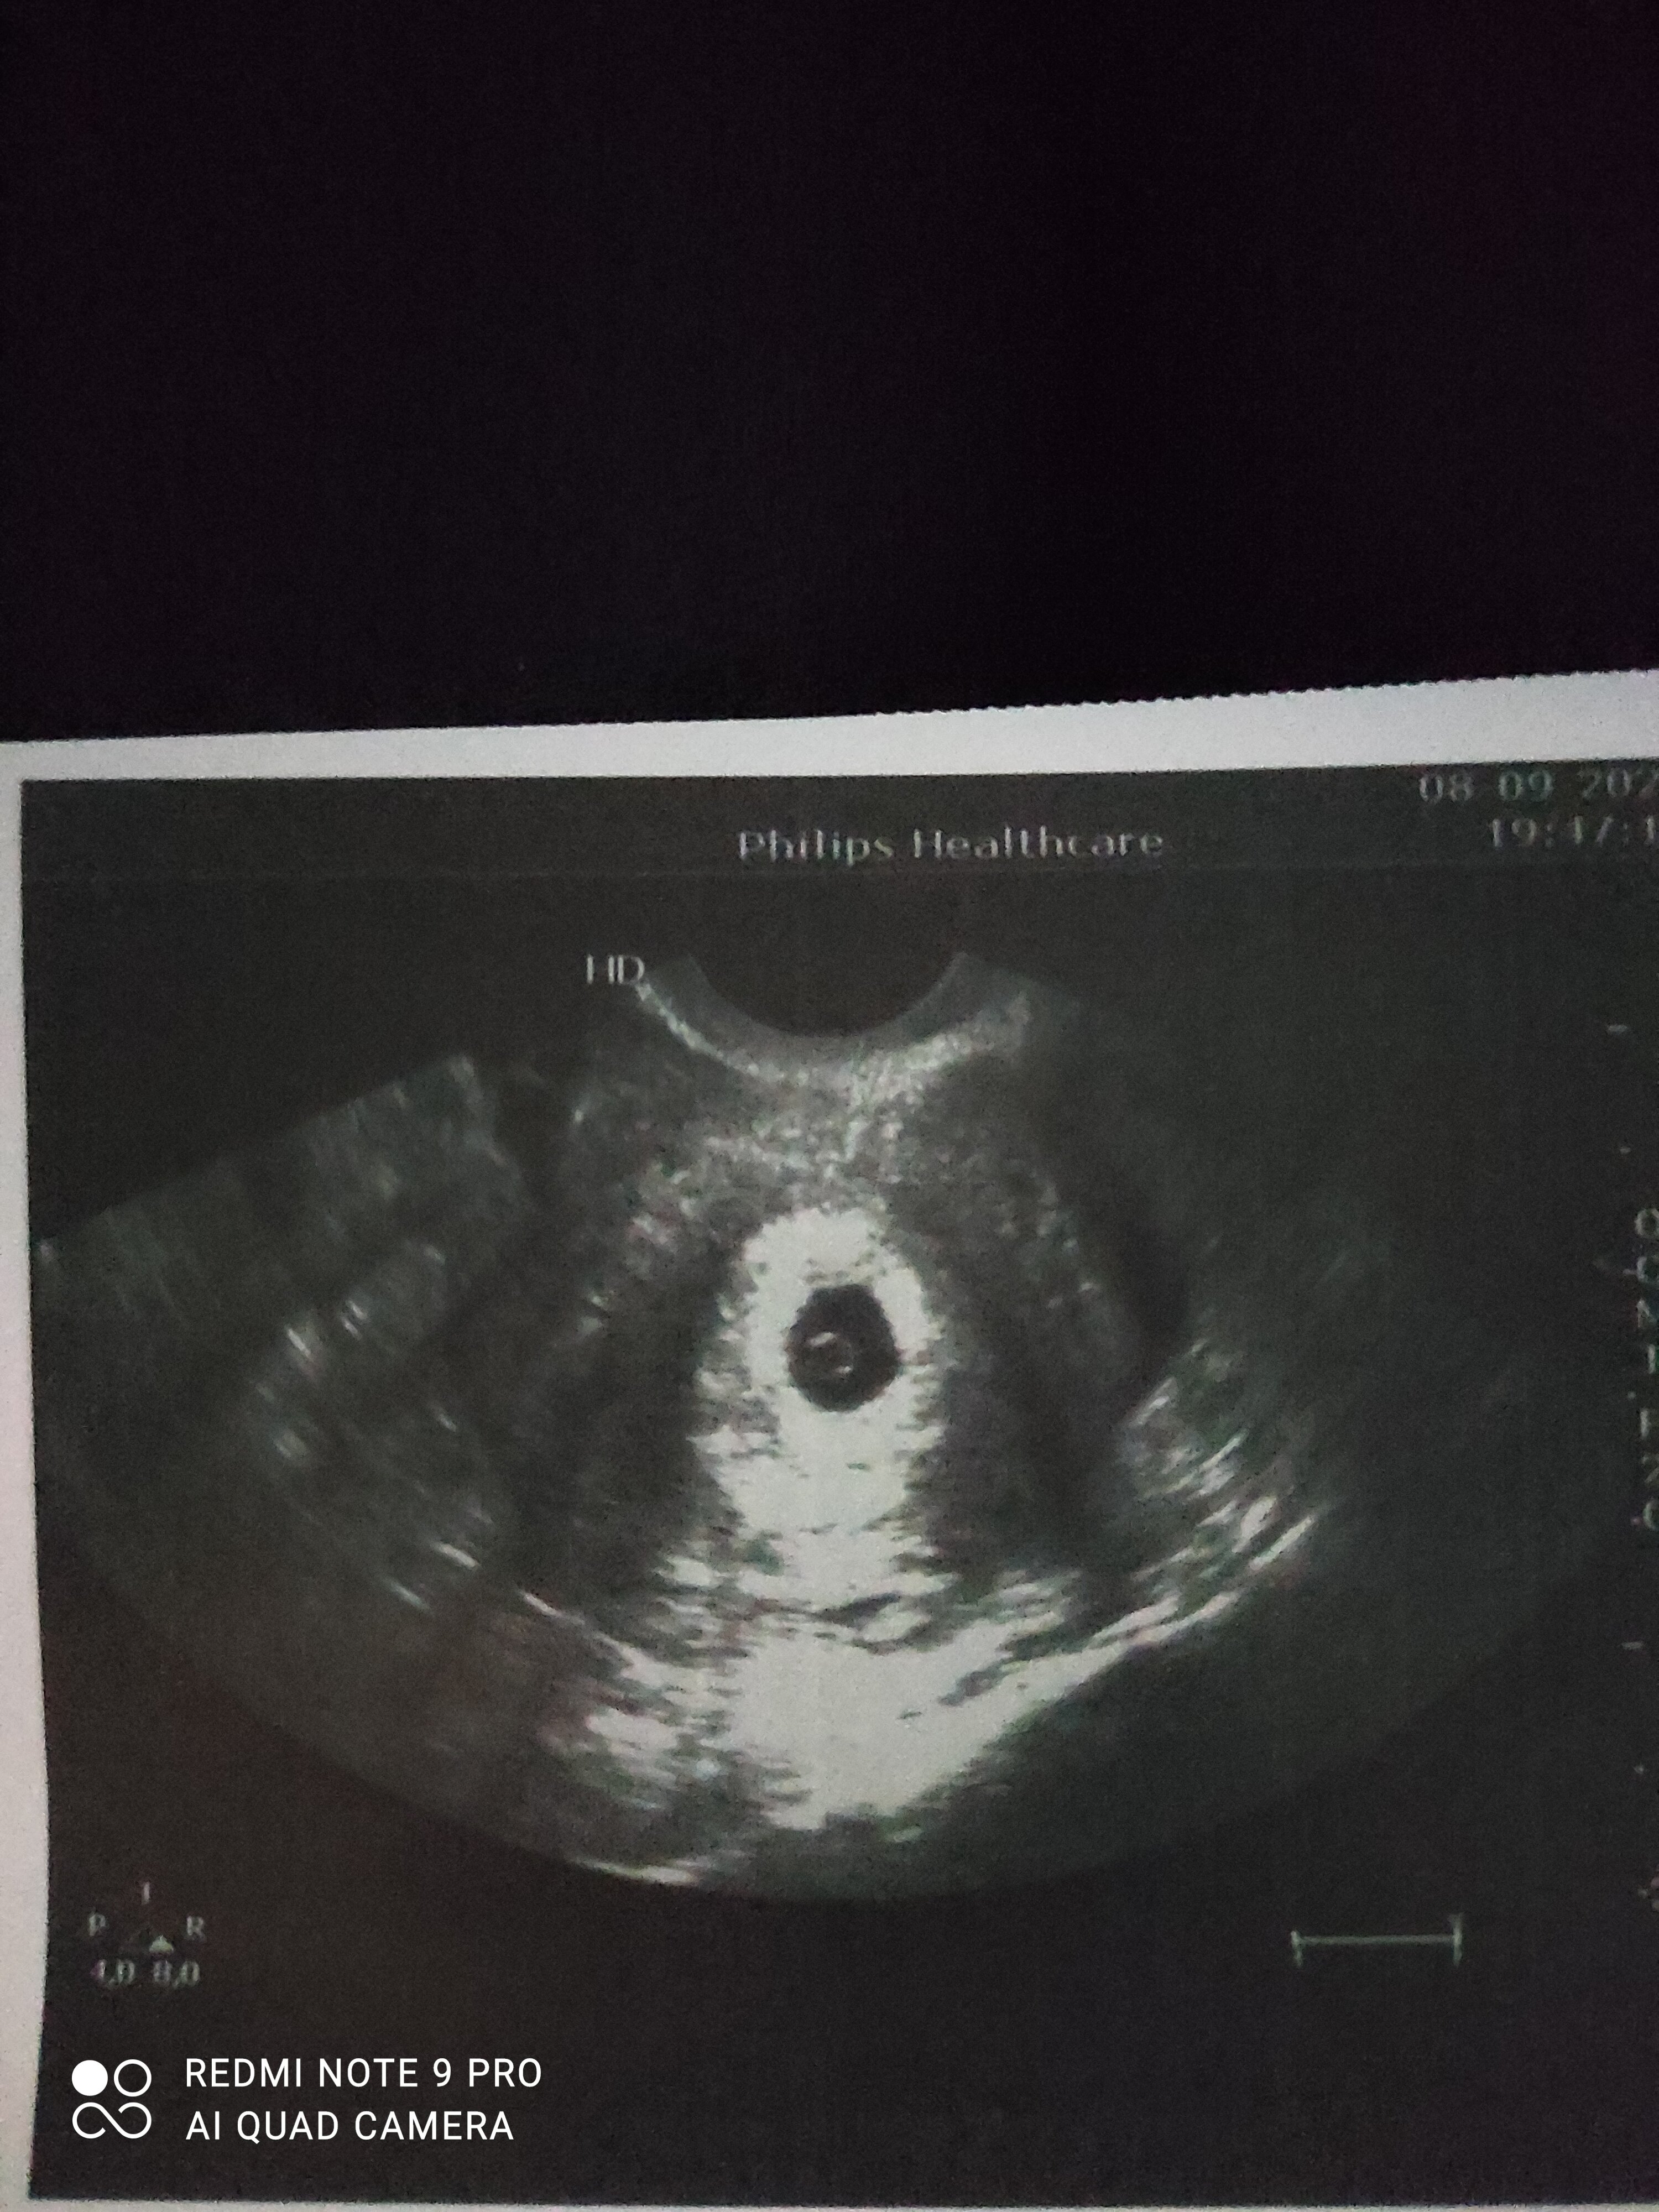

Super! Czy ja tam widzę zarodek ?Ja już po dziewczynywszystko dobrze a le zapisał dużo leków żeby utrzymać ciążę po tylu poronieniach

Tak było ale takie cichutkie aż się popłakałamSerduszko było?

Tak był zarodek i cichutkie serduszkoOjeju biedactwojakieś leki dostaliście ?

Super! Czy ja tam widzę zarodek ?Widziałaś serduszko?